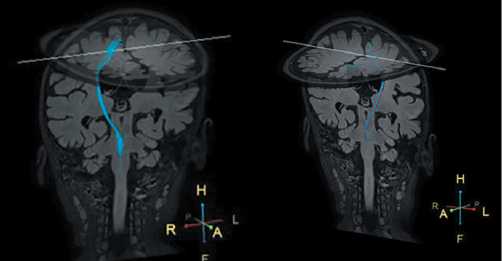

Only single projections originated from SMA were seen in the left hemisphere (Fig. 1).

Fig. 1. MR tractogram with CST reconstruction of patient S. on day 56 from injury.

Single CST projections from SMA (blue) are seen on the left (arrows).

During the follow-up 6 months from injury, MEPs could not be reliably verified, although even a single stimulus of 50% intensity triggered a 25-sec generalized tonic seizure. Therefore, the number of stimuli was limited. CST reconstruction on follow-up MR tracto graphy demonstrated substantial volume predominance of the right CST originated from SMA and absence of CST from M1 (Fig. 2).

Fig. 2. MR tractogram of patient S. in 6 months from injury. Predominance of CST originating from right SMA (blue).